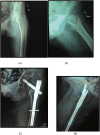

Introduction: Intertrochanteric fracture is one of the most common and severe fractures occurring in the elderly population. We conducted a randomized prospective study to compare the functional and radiological outcome of Proximal Femoral Nail anti-rotation-Asia(PFNA-II) and Dynamic Hip screw (DHS) used in fixation of stable (AO type 31 A1-A2.1) intertrochanteric fractures in elderly.

Methods: 60 elderly patients with stable intertrochanteric fractures treated with DHS and PFNA-II between August 2014 to Dec 2016 were enrolled in the study. Intraoperative variables-surgical time, blood loss, fluoroscopy time and post-operative variables-union rate, change in neck shaft angle(NSA), functional outcome in terms of Modified Harris Hip Score(HHS) & SF-12, complication rate and mortality at one year were studied and compared between both the groups.

Results: The mean age of patients in our study was 70.96 years. We found patients treated with DHS required significantly longer surgical time and had more blood loss compared to PFNA-II group. However, there was no significant difference in both the groups in terms of intra-operative fluoroscopy time, change in neck shaft angle, union rate, complication rate and Modified Harris Hip Score & SF-12 at three months; six months and one year follow-up.

Conclusions: Both DHS and PFNA-II can be used effectively in the treatment of elderly patients with stable intertrochanteric fracture with comparable outcome. However, in high-risk elderly patients requiring shorter surgical time and less blood loss, PFNA-II can be used.